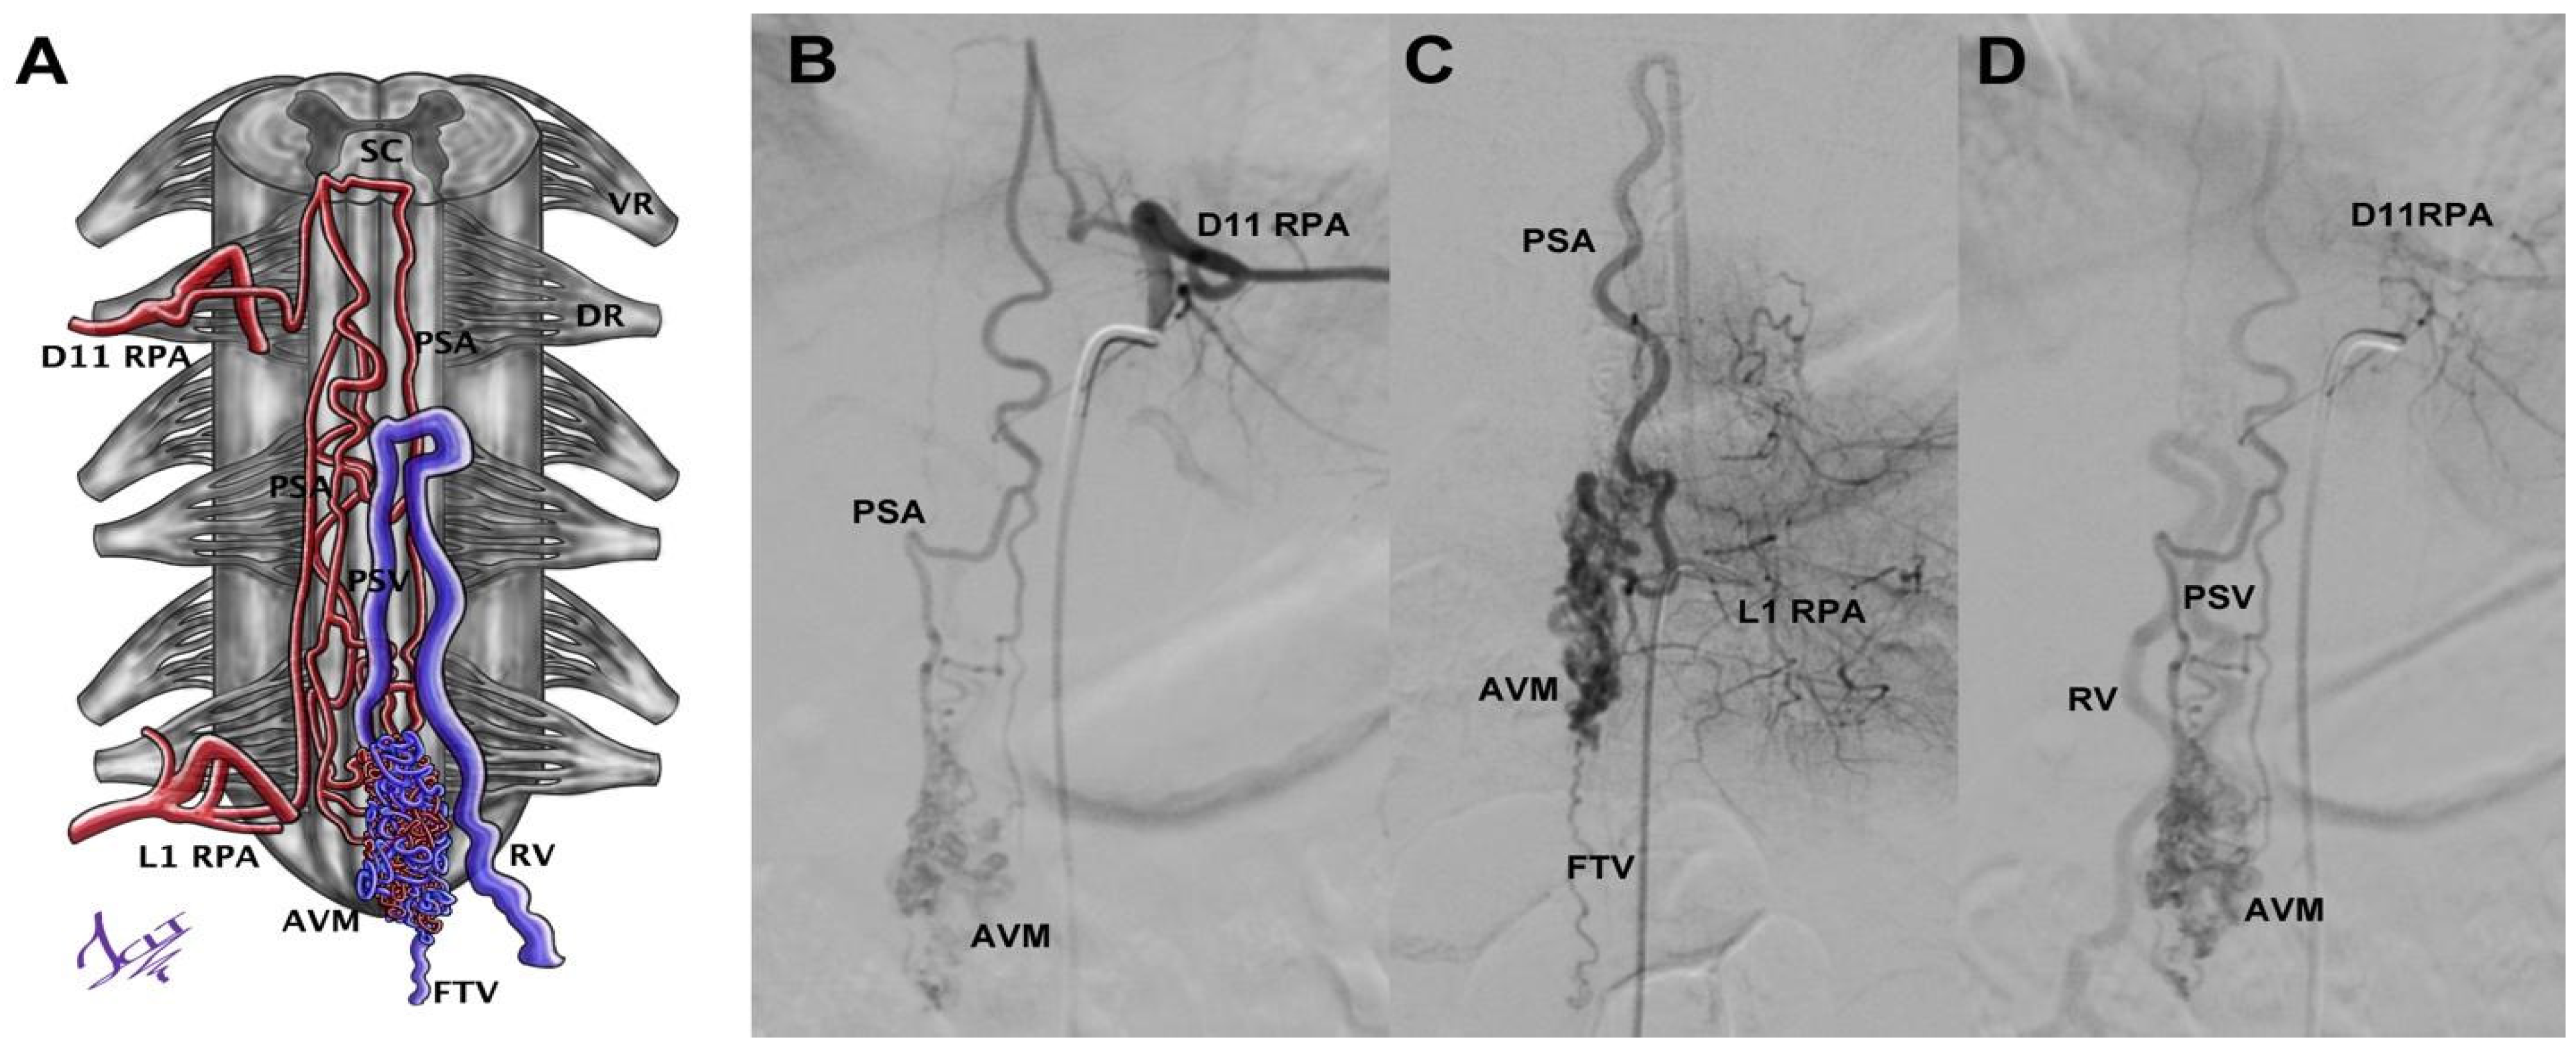

Case 10 was an 18-year-old male with sudden lumbar pain, paraparesis, headache, and nausea. Brain CT showed subarachnoid hemorrhage (SAH), and sDSA displayed a vascular lesion. The nidus was located from D12 to L2, and the afferents proceeded from left D11 and left L1 (radiculopial arteries (RPAs) and PSA); its drainage was through the radiculomedullary vein (RMV) (Figure 4). However, the Wada test performed in L1 was positive, and we decided to embolize the left D11 afferent with Histoacryl. Four months later, a new Wada test through left L1 was negative, so we proceeded to embolize with Histoacryl, achieving total occlusion of the sAVM without injury.

Figure 4.

A compact AVM of the medullary cone schematized (A) from the angiographies through the left intercostal artery at the D11 level (B), the left lumbar artery at the L1 level (C), and their venous phase (D). RPA = radiculopial artery, AVM = AVM nidus, PSA = posterior spinal artery, DR = dorsal root, VR = ventral root, PSV = posterior spinal vein, RV = radicular vein, SC = spinal cord, FTV = filum terminale vein. Illustrated by J. Lizana.